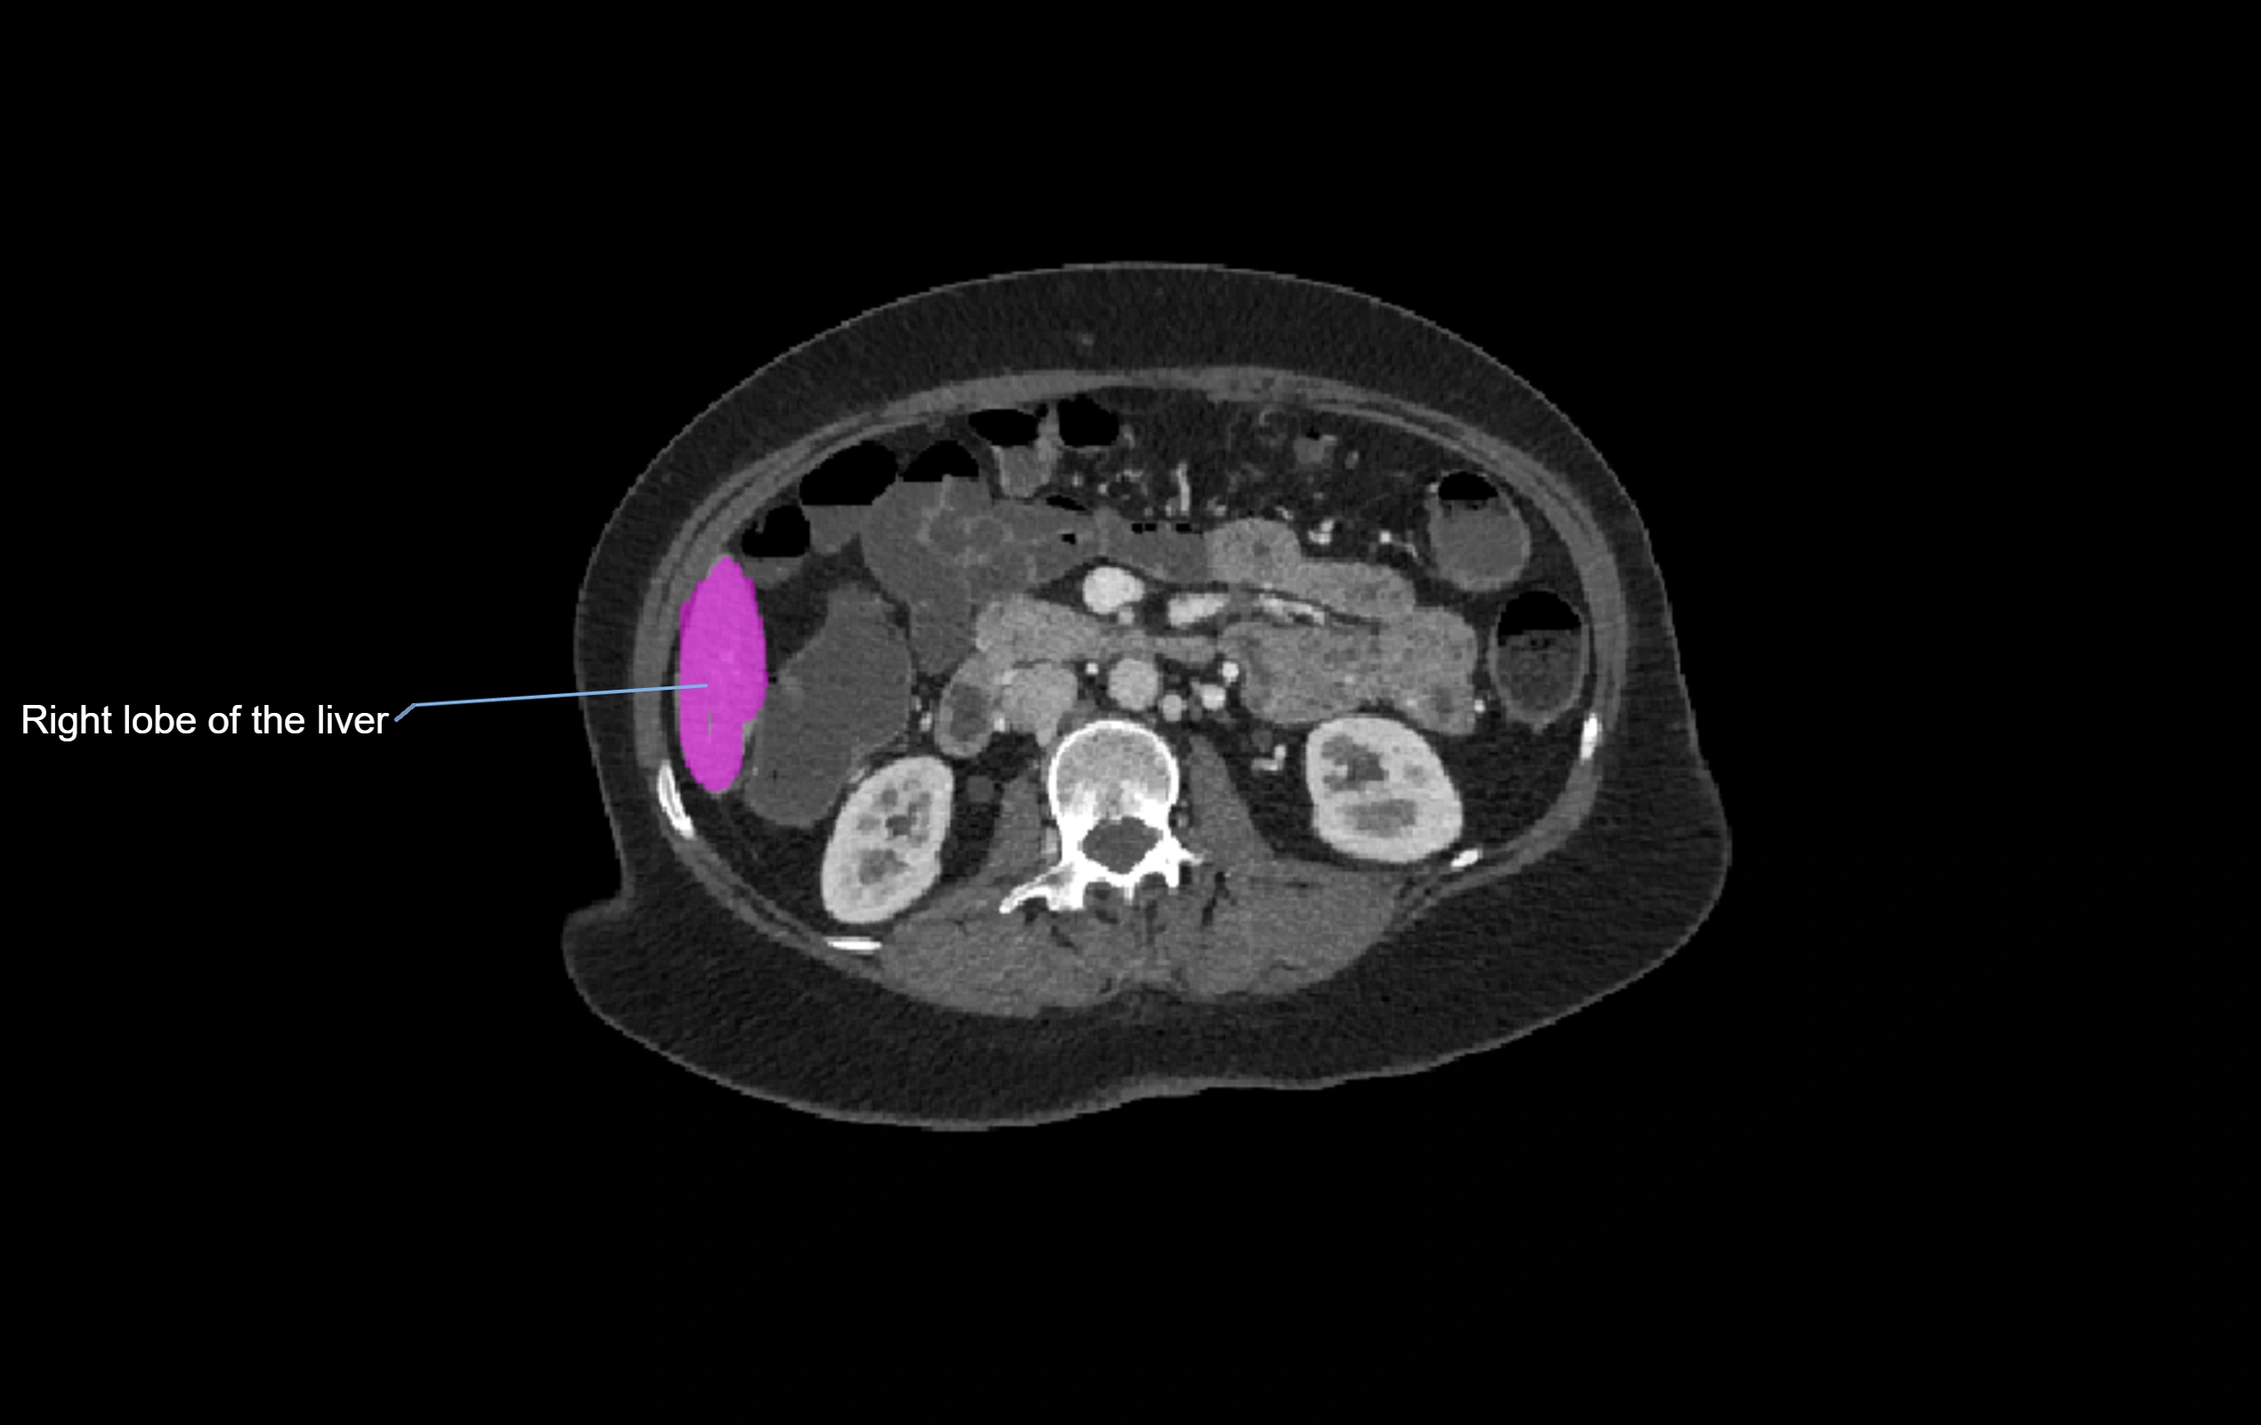

CT Image

image